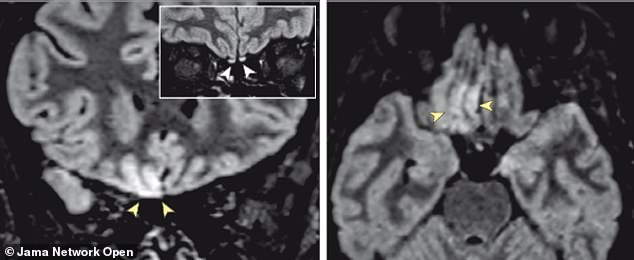

Las flechas indican la zona del cerebro afectada por el virus

La pérdida del olfato puede presentarse en los dos tercios de los contagiados con el coronavirus, como en este caso. Los cambios en el cerebro fueron observados en una paciente de 25 años que perdió el sentido del olfato, sin presentar otros síntomas notorios.

Sus fosas nasales y el pecho eran normales después del examen, pero una resonancia magnética mostró daños en partes de su cerebro involucradas en el sentido del olfato. Es la primera vez que una resonancia magnética muestra los cambios en el cerebro causados por el coronavirus.

Las imágenes muestran ligeras fluctuaciones en un área del cerebro que controla nuestro sentido olfativo. Expertos médicos del Instituto Clínico Humanitas del IRCCS y la Universidad Humanitas en Milán, Italia, y Boston Children’s en los Estados Unidos, señalan que las alteraciones se ven con claridad, aunque no sean tan claras para el común de la gente.

Encontraron cambios en su cerebro en dos áreas: una región llamada giro recto derecho y en los bulbos olfativos, que son los que toman información sensorial de la nariz y la pasan a otras regiones, incluido el giro recto, para su procesamiento.

La forma en que estos cambios aparecieron en la resonancia magnética fue consistente con el tipo de imágenes que los médicos esperarían ver de los ataques virales en el órgano, por lo que analizaron a la mujer para detectar coronavirus. Su prueba fue positiva.

Después de 28 días, los médicos hicieron otra resonancia magnética y pudieron ver que su cerebro comenzaba a volver a la normalidad, aunque los bulbos olfatorios permanecieron ligeramente inflamados. Finalmente, el sentido del olfato de la mujer volvió y no se vio ningún daño a largo plazo.